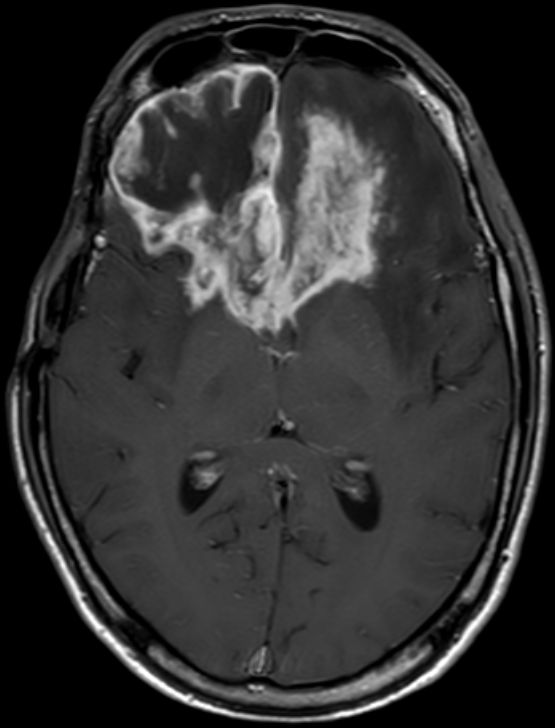

Glioblastom als Rezidiv eines Astrozytoms |

36-jähriger Mann, der vor 7 Jahres ein rechts-frontales Astrozytom Grad II mit Übergang in ein anaplastisches Astrozytom III hatte.![]() |

Jetzt Krampfanfall. Das MRT zeigt ein großes frontales Schmetterlingsgliom.![]() | |||

Die MRT-Kontrolle mit KM vor einem Jahr zeigt eine unauffällige Resektionshöhle.![]() |